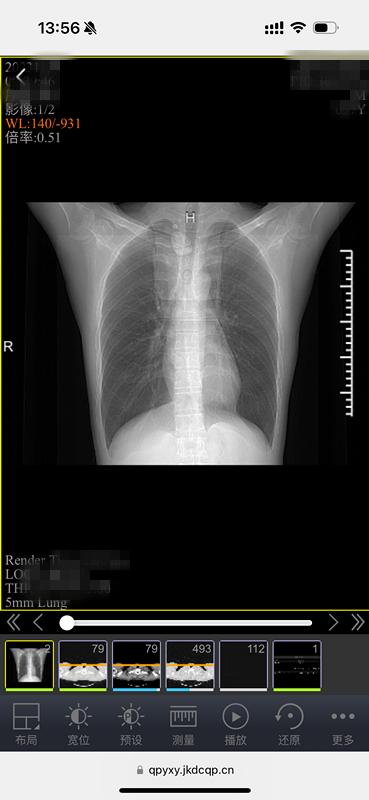

原来,这是中山医院青浦分院为方便百姓就医、优化就诊流程,推出的又一项便民措施——“电子胶片”智慧医疗服务。放射科主任武刚介绍,所谓“电子胶片”,就是患者在中山医院青浦分院做了放射DR、CT、磁共振等检查后,无需再去窗口等待打印传统胶片,用手机、ipad等移动终端扫描报告单上的二维码,检查的影像资料就可以全部在手机上显示,临床医生也可以使用电脑查看影像资料。

电子胶片,不光保存方便,携带方便,医生还能看原始数据。什么叫原始数据?简单地说就是“电子胶片”包含全部图像,支持对图像进行放大缩小、调节明暗等专业操作,能更好地看清病灶,更利于诊断。